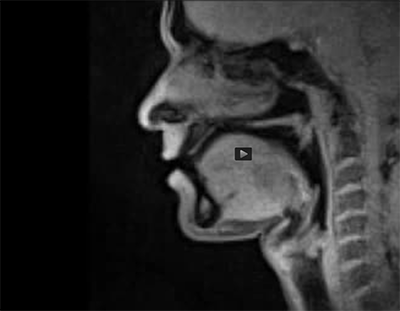

MRI of speech

Click to watch speaking in an MRI